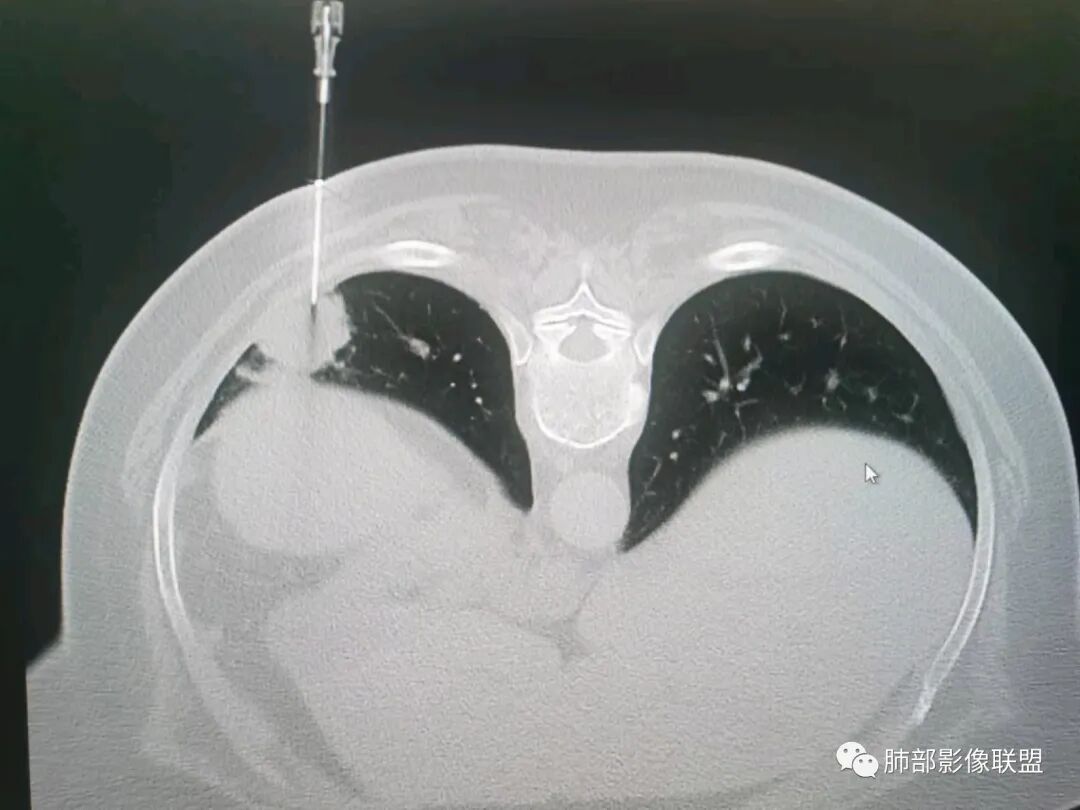

01  病例资料

秦化君:左肺下叶外基底段胸膜下软组织密度结节性,边缘毛糙与血管相连,密度不均,增强后病灶内边界不清低密度区,胸膜栽桩,少量胸腔积液。考虑恶性病变,腺癌可能。真菌待排。

谢加平:老年女性,慢性咳嗽,咳白痰史,左肺下叶后基底段胸膜下肿块,类圆形,边界清膨隆,密度不均匀,低强化及小灶性坏死,坏死轮廊不清,胸膜下栽赃明显,左侧胸腔少量积液,向胸壁肌侵犯,另肿块近心侧见支指套征,粘液低密度,支持恶性,粘液腺Ca,经皮肺穿刺活检明确诊断。

361度:老年女性,发热,胸部CT示左下肺胸膜下结节影,血管集束,毛棘,密度不均,胸膜栽赃,少量胸腔积液,不均匀强化,坏死边界不清,肿标轻微升高,考虑恶性,鳞癌合并感染。

红星:老年女性患者。胸膜下结节病变,明显的膨胀,并局部侵犯胸膜,增强明显的强化。病灶周围带有局灶的渗出性改变以及条索上的影。考虑腺癌的可能性大,鉴别结核肉芽肿性病变。

春秋:左肺下叶胸膜下结节,边缘平直,内见低密度区,胸膜下胸腔积液相隔,考虑炎性结节可能性大,伴小脓肿形成。

宇宙:左肺下叶胸膜下球形肿块,边界尚清,局部平直,局部膨隆,内侧缘长索条,胸膜栽赃,轻度不均匀强化,其内坏死边界欠清,左侧胸水,考虑腺癌,鉴别放线菌。

党医生:左下肺结节,整体呈不完全规则、局部呈球形结节,有较长、轻大的条索壮改变,球形病变区域与胸膜呈宽基底,密度不均匀、有液化低密度区,不均匀强化,总体分析考虑:结核可能大,其次炎性假瘤,肺癌可能小。

摘星空竹子:左肺下叶后基底段与外基底段交界处胸膜下椭圆形软组织肿块,边界尚清,密度欠均匀,患侧少量胸腔积液,增强扫描轻度或无强化,肿块中央可见斑片状低密度区,边界尚清,考虑OP伴脓肿或结核,鉴别腺癌。

李庆东:左肺下叶外基底段胸膜下球形软组织密度,边缘毛糙与血管相连,轻度强化,增强后病灶内边界不清低密度区,宽基底于胸膜,少量胸腔积液。考虑良性病变,炎性假瘤可能大。特殊感染待排,鉴别腺癌。

袁媛:左肺下叶胸膜下球形肿块,宽基底连于胸膜下,胸膜栽赃,边缘膨隆,有血管供应,增强有强化,考虑腺癌。

gaoql:倾向肿瘤,胸膜下脂肪间隙受累,有细角和nse升高,如果男性,要考虑鳞癌,但是个女性,还是先考虑腺癌的可能。感染指标升高,还需鉴别炎性肉芽肿性病变,能累及胸膜下间隙的,要鉴别脓肿或放线菌。

看图说话:胸膜下肿块,密度不均,边缘毛糙,增强后不均匀强化,胸膜栽赃,左侧胸腔积液,腺癌,鉴别肉芽肿。

songml:老年女性,反复咳嗽咳痰胸闷4年,加重伴发热一周。左肺下叶后基底段胸膜下肿块影,密度较均匀,边缘较清,侵及胸膜下脂肪间隙。考虑恶性病变,腺癌可能,鉴别真菌感染。

人生海海:左肺下叶不规则形软组织密度影,膨隆生长,边缘清楚,分叶,棘突征,支气管截断,血管纠集,病灶轻度强化、内多发坏死,左侧少量胸腔积液,考虑粘液腺癌,鉴别肺脓肿。

位移:老年女性,左肺下叶肺胸膜下团块影,边界清、毛糙,膨隆,内密度不均,不均匀强化,内见坏死,胸膜栽赃,胸腔少量积液,首先考虑恶性肿瘤,低分化腺癌,鉴别小细胞癌,炎性假瘤。

赖晓宇:膨隆,浅分叶,支气管截断,内部坏死边界不清,胸膜受累,胸腔积液,考虑恶性。

枷黎:左肺底类圆形结节,略分叶,毛刺不明显,周围似乎有淡淡的晕,增强扫描呈较均匀轻度强化。结合临床症状和实验室检查,首先考虑炎性肉芽肿类病变可能,肿瘤待排。

赵:增强病变与胸膜分界清晰,平扫密度左侧胸腔密度高能否是慢性炎症刺激引起,坏死边缘清晰,提示病变强化明显。临床实验室检查血象增高先考虑慢性炎症,腺癌待除外。

许慧良:老年女性患者,左肺下叶后基底段胸膜下结节影,边界清楚,密度不均匀,内部有低密度影,边缘有结节颗粒感,对胸膜有黏连牵拉感,考虑恶性,腺癌可能。

王静:左肺下叶病变,紧贴胸膜,楔形,尖端朝向肺门,临近胸膜未见明显增厚,胸腔少量积液,增强扫描病变内部不均匀强化,可见边界相对清晰液化坏死区。患者有发热病史,血象高。诊断,左肺下叶炎性肌纤维母细胞瘤可能,鉴别肉芽肿性病变。

梦妮6-1:老年女性,慢性咳嗽,咳白痰史,左肺下叶后基底段胸膜下肿块,类圆形,边界清膨隆,密度不均匀,中间有低强化及小灶性坏死,边界清,有胸水,病肺门侧有支管通过,胸膜界线清,考虑良性病可能。隐球菌?

WXD:左肺下叶胸膜下占位性病变,整体强化还是比较明显,中心坏死边界较清晰,还是先考虑炎性肉芽肿性病变,鉴别炎性肌纤维母细胞瘤。

良孑:左肺下叶胸膜下结节,可见晕征及软毛刺,边缘有锯齿状浅分叶,其内坏死边界不清,均匀性低强化,局部层面边缘可见平直及u型凹陷,胸膜糊墙并少量积液,慢性病史急性发作,炎性标志升高,首选炎性肉芽肿性病变,0P并脓肿,高龄,有锯齿状浅分叶腺癌也难以除外。

瑞欣:左肺下野胸膜下高密度灶,边界较清,宽基底与胸膜相贴,胸膜增厚,强化可见病灶内低密度区坏死区,胸膜没有栽赃,首选考虑炎性肉芽肿,鉴别腺癌。

笑微微:左肺下叶外后基底段见结节影,密度不均,边缘欠光整见浅分叶及棘样突起,病灶与相邻胸膜分界不清并见胸膜不均匀性增厚,增强呈不均匀强化,左侧见少量积液。考虑腺癌,鉴别结核。

放射线:左肺下叶后基底段胸膜下肿块,边缘膨隆,密度不均匀,内见低密度坏死,胸膜栽赃,左侧胸腔少量积液,考虑恶性,腺癌?鉴别放线菌,OP伴脓肿。

仲夏:老年女性,咳嗽咳痰近4年,左肺下叶胸膜下类圆形肿块,内侧绳索征,内部密度不均匀,可见坏死,周围小空泡,小叶间隔增厚,胸膜下积液,轻度强化,NSE、细胞角蛋白酶19片段高,考虑恶性肿瘤,腺癌?

许慧良:老年男性患者,左肺下叶后基底段胸膜下结节影,边界清楚,密度不均匀,内部有低密度影,边缘有结节颗粒感,对胸膜有黏连牵拉感,考虑恶性,腺癌可能。

AAA张春雨:左肺胸膜下大小不等的多发病灶,内有支气管半进入征,强化内部不均,患者有明显肺气肿背景,胸阔呈桶状,少量胸腔积液,综合考虑隐球菌感染的可能性最大,鉴别腺癌。